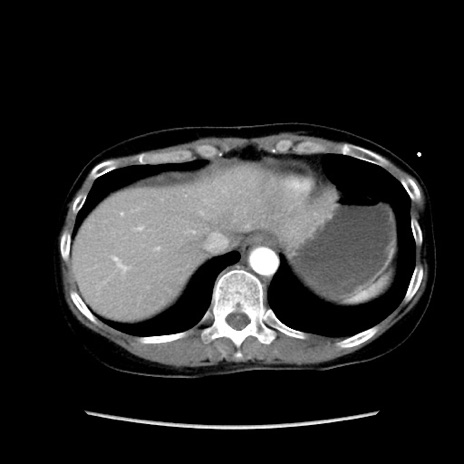

症例32(横断像)

【症例】40歳代 女性

【主訴】上腹部痛、嘔気・嘔吐

【現病歴】約9時間前頃から急に上腹部痛、嘔気、嘔吐が出現。改善しないため救急要請。

【既往歴】子宮頚癌(広汎子宮全摘術、放射線療法)、腸閉塞

【身体所見】腹部:平坦、軟、腸雑音亢進、上腹部を中心に腹部全体に圧痛あり。

【データ】WBC 8400、CRP 0.03